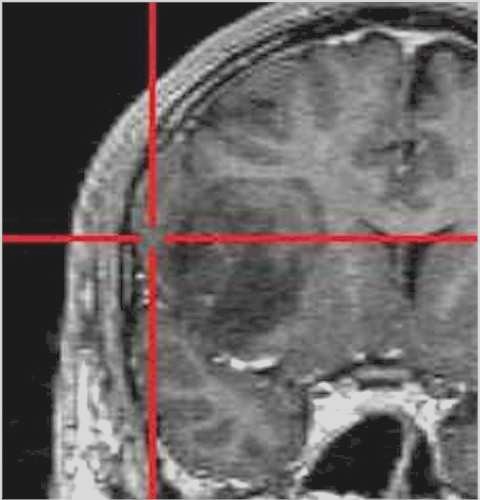

La neuronavigazione comprende sistemi computerizzati avanzati che consentono al chirurgo di conoscere in ogni momento l’esatta posizione dei propri strumenti durante l’intervento chirurgico, permettendo oggi di raggiungere praticamente qualsiasi sede intracranica mediante approcci spesso innovativi e meno invasivi.

Questi sistemi svolgono a tutti gli effetti anche una funzione stereotassica, poiché consentono di localizzare un bersaglio intracranico all’interno di un sistema di coordinate tridimensionali derivato dalle immagini di Risonanza Magnetica o Tomografia Computerizzata, con un’elevata accuratezza spaziale. In tal senso, la neuronavigazione può essere considerata una

stereotassia frameless, che non richiede l’applicazione di un casco stereotassico rigido, garantendo maggiore flessibilità e comfort per il paziente.

Il procedimento ha inizio con l’esecuzione di una Risonanza Magnetica (RM) o di una Tomografia Computerizzata (TC) del paziente, effettuate mediante protocolli di acquisizione dedicati.

Al momento dell’intervento chirurgico, il capo del paziente viene registrato nello spazio tridimensionale del computer tramite un sistema di localizzazione, generalmente ottico a infrarossi, che riconosce specifici punti di repere applicati al capo o al sistema di fissaggio.

Il computer provvede quindi a sovrapporre l’anatomia reale del paziente alle immagini RM o TC precedentemente acquisite. Durante l’intervento, il chirurgo utilizza strumenti chirurgici dotati di marker che vengono continuamente rilevati dallo stesso sistema ottico a infrarossi; in questo modo il neuronavigatore è in grado di indicare in tempo reale, sulle immagini RM o TC, l’esatta posizione degli strumenti all’interno del campo operatorio.

Grazie a questa tecnologia, l’intervento viene accuratamente pianificato alla consolle del computer, anche nei giorni precedenti l’atto chirurgico, consentendo di valutare in modo approfondito il percorso di accesso più sicuro e riducendo significativamente il rischio di dover effettuare scelte intraoperatorie non sufficientemente ponderate.

Per raggiungere una determinata sede, anche se profonda o localizzata in aree critiche, è possibile adottare traiettorie talvolta più lunghe ma che attraversano regioni cerebrali a minore rischio funzionale per il paziente. In questo modo sono venuti meno molti dei limiti legati alla difficoltà di accesso anatomico (lesioni profonde, sedi eloquenti), che in passato spesso precludevano un trattamento chirurgico.

Localizzazione

dell'area con il neuronavigatore |